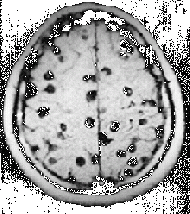

Magnetic resonance image of a patient with neurocysticercosis demonstrating multiple cysticerci within the brain. | |

Cysticercosis is a parasitic disease caused by infection by the pork tapeworm, Taenia solium, in which the tapeworm enters the body and forms cysticerci (larval form of the tapeworm enclosed in a cyst, or fluid-filled protective capsule). When the infection results in cysticerci in the brain and spinal cord, the condition is known as neurocysticercosis. Cysticercosis is the most common parasitic infestation of the central nervous system worldwide.

Cysticercosis (SIS-tuh-sir-KO-sis) is the term for infections of T. solium resulting in cysticerci. Cysticerci are commonly found at autopsy in asymptomatic inhabitants of endemic areas. In humans, cysts can cause serious sequelae if they localize in the brain, resulting in neurocysticercosis.

The most dangerous symptoms are a result of encystment in the central nervous system. According to a Centers for Disease Control and Prevention Division of Parasitic Diseases in neurocysticercosis (cysticercosis of the brain), the most common symptoms are seizures and headaches, but other symptoms can include confusion, difficulty of balance, lack of attention to people and surroundings, and hydrocephalus (compression of the brain tissue due to obstruction of cerebrospinal fluid flow) (CDC 2008). With heavy infections, death can occur (CDC 2008).